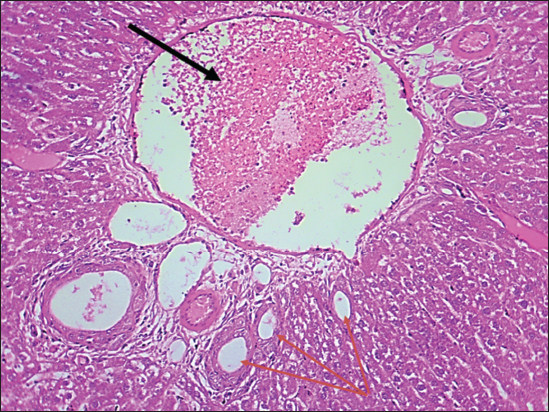

Fig. 4. Histological section of the liver of rats drenched with 0.6 mg/kg citalopram. The section shows a mild degenerative lesion (fatty degeneration, black arrows) with fibrous network formation in parenchyma (red arrow), (H and E stain 100X).

The results of this study revealed no significant differences in bilirubin levels in all treated animals (Table 1), whereas serum ALT and AST levels showed significant elevations in all treated animals either by citalopram alone (fourth group) or with J. regia pulp extract at doses of both 10 and 20 mg/kg (Tables 2 and 3). Sections of histopathological study appeared as mild degenerative lesions characterized by infiltration of fat droplets inside hepatic cells, which gave them a ring shape appearance due to pushing the nucleus at one side from the hepatic cells with fibrous networks formation in the tissue parenchyma, infiltration of structureless, homogenous, and pinkish material (Figs. 16). Clear hepatic vein congestion and narrowing in the hepatic artery and arteriole diameters revealed that citalopram caused liver dysfunction and injury (Figs. 79).

These results correspond with those of other studies, in which patients treated with antidepressants appeared to have moderately elevated levels of the aminotransferase. All antidepressants caused hepatotoxicity; citalopram is that have the least potential for hepatotoxicity, which is characterized by high alanine aminotransferase levels (Gartlehner et al., 2008; Voican et al., 2014; Ilgın et al., 2020). The results of this study revealed no significant differences in bilirubin levels in all treated animals as the level of p < 0.05, serum ALT and AST levels showed a significant elevation in all treated animals either by citalopram only (fourth group) or with J. regia pulp extract at doses of 10 and 20 mg/kg B.W. Sections of histopathological sections show mild degenerative lesions characterized by infiltration of fat droplets inside hepatic cells, which give them a ring shape appearance due to pushing the nucleus at one side from the hepatic cells with fibrous networks formation in the tissue parenchyma, infiltration of structureless, homogenous, and pinkish material (Figs. 4 and 6). Clear hepatic vein congestion and narrowing in the hepatic artery and arteriole diameters revealed that citalopram caused liver dysfunction and injury (Figs. 79).